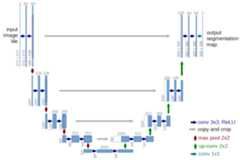

Implementation of different kinds of Unet Models for Image Segmentation - Unet , RCNN-Unet, Attention Unet, RCNN-Attention Unet, Nested Unet

Implementation of different kinds of Unet Models for Image Segmentation

UNet - U-Net: Convolutional Networks for Biomedical Image Segmentationhttps://arxiv.org/abs/1505.04597

RCNN-UNet - Recurrent Residual Convolutional Neural Network based on U-Net (R2U-Net) for Medical Image Segmentationhttps://arxiv.org/abs/1802.06955

Attention Unet - Attention U-Net: Learning Where to Look for the Pancreashttps://arxiv.org/abs/1804.03999

RCNN-Attention Unet - Attention R2U-Net : Just integration of two recent advanced works (R2U-Net + Attention U-Net)

- Nested UNet - UNet++: A Nested U-Net Architecture for Medical Image Segmentationhttps://arxiv.org/abs/1807.10165

Implementation of different kinds of Unet Models for Image Segmentation - Unet , RCNN-Unet, Attention Unet, RCNN-Attention Unet, Nested Unet